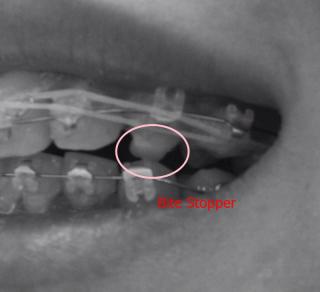

Then cos my upper gigi taring is hitting my lower teeth that causing the bracket to come loose. Then doctor put the bite stopper on the gigi taring.

Last month, doctor put bite stopper on my upper gigi geraham up til to date, and now i can speak and eat better compared to last month. When I speak last month, because the upper and lower teeth don't touch (there's a gap between upper and lower teeth), I speak as though I have short tongue haha...

Yes, its quite complicated. I think we are in the same boat. Anyways, for those who are curious, click spoiler below for pictures.

» Click to show Spoiler - click again to hide... «

I had the pics in B/W cos i dun wanna gross you out... blush.gif